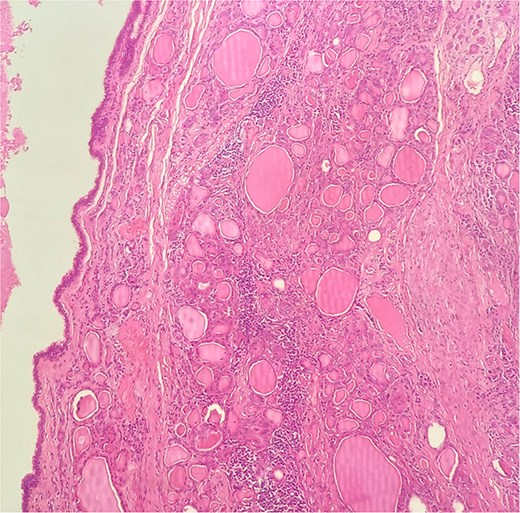

A 47-year-old woman with unremarkable medical history, presented with a 2 months history of neck mass along the midline. Physical examination revealed a 6 cm mobile, thyroid nodule without compressive symptoms. There was no associated erythema, fluctuance, tenderness or adhesion to adjacent structures. There was also no associated cervical lymphadenopathy. The rest of the physical exam was unremarkable. Laboratory tests including TSH, FT3, and FT4 revealed normal levels. On cervical ultrasound, there were a 62 mm left toto-lobar nodule classified as EU-TIRADS3, and an 11 mm right nodule, also classified as EU-TIRADS3. Fine-needle aspiration cytology concluded to a benign lesion classified as BETHESDA II. The patient reported respiratory discomfort in the supine position, leading to the indication for a lobectomy. Gross examination of the specimen revealed a toto-lobular nodule with a colloid appearance. It was well-circumscribed by a thin and regular fibrous capsule. The nodule measured 4 × 6 cm and exhibited areas of fibrous, whitish remodeling, as well as hemorrhagic and cystic changes. On microscopic examination, the nodule corresponded to a macro vesicular adenoma altered by fibrosis and hemorrhage. It was surrounded by a thin, regular, and intact fibrous capsule. However, at the periphery of the nodule, adjacent to the thyroid pseudo capsule, a 1.2 cm cystic ductal structure was observed. It showed pseudostratified ciliated columnar and squamous epithelial lining associated with thyroid follicles in the surrounding stroma (Figs 1 and 2). These thyroid follicles were bland with no papillary nuclear atypia or invasion (Fig. 3). The cyst was filled with a thin eosinophilic material (Fig. 4) Lymphocytic thyroiditis of mild severity was identified in the rest of the thyroid tissue. Based on these findings, the diagnosis of macro vesicular thyroid adenoma with ITTGDC and lymphocytic thyroiditis was made. After the surgery, the patient developed temporary dysphonia.